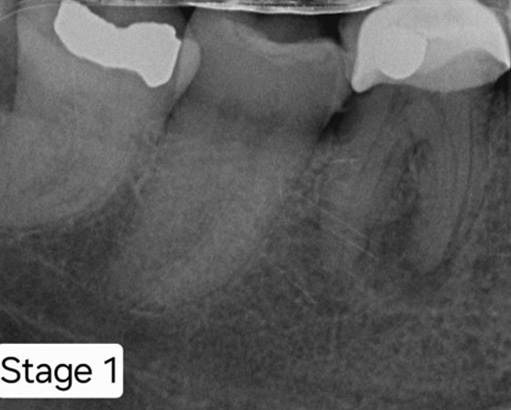

Pathology present in the Lower Left 7 – the patient was motivated to save the tooth.

RCT completed with posts placed.